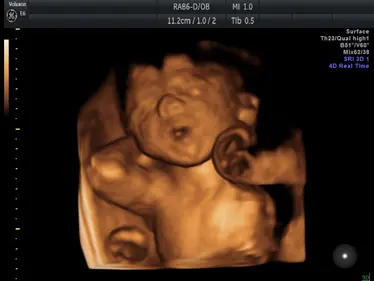

Gallery: 4D Scan Images & Videos

All of the baby scans we perform here at First Encounters are carried out using top-quality ultrasound equipment. For 3D/4D scans, we use the GE Voluson E6, featuring genuine HDLive technology. GE Healthcare are the world’s leading providers of pregnancy scanning equipment, and HD Live scans give an unparalleled level of detail and clarity.

Scroll down to view some examples of the 4D scan images and videos our sonographers are able to capture.

4D Scan Videos

We can also record motion video clips during your 3D/4D scan. Here are some of the 4D scan videos our trained sonographers have captured during real ultrasound scans: